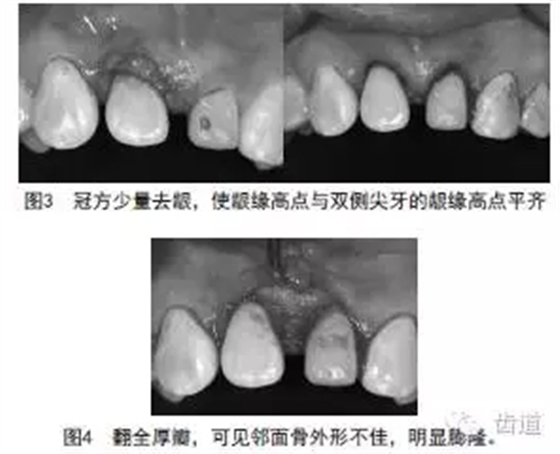

①向患者交代手術(shù)方案及風(fēng)險,簽知情同意書;患者目前處于皰疹感染期,建議擇期手術(shù),患者因工作忙,堅持今日手術(shù)。②常規(guī)消毒鋪巾。③12和22在復(fù)方鹽酸阿替卡因(含腎上腺素)局部麻醉下(STA無痛麻醉)下,冠向距齦緣約1~2mm內(nèi)斜切口,齦緣高點與13和33平齊(圖3),溝內(nèi)切口,翻黏骨膜全厚瓣,暴露牙槽嵴頂,可見12和22牙間隙處牙槽嵴頂略凸(圖4),與齦緣約2~3mm,12和22唇側(cè)近中渦輪去骨約0.5~1mm,骨成形,未降低骨高度(圖5),牙齦修整,牙間乳頭處5/0不可吸收線間斷縫合3針(圖6),上牙周保護劑。④醫(yī)囑:0.12%復(fù)方氯己定溶液漱口,每日2次,1周;口服抗生素3天,積極控制皰疹感染。⑤1周后拆線。